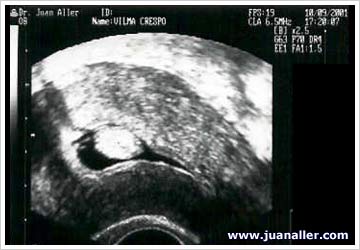

WAB 14-2: SONOHISTEROGRAFÍA - PÓLIPOS

Pólipo pediculado

Pólipo sesil

Pólipos múltiples

Pólipo en cicatriz de cesárea anterior

Pólipo que simula un mioma